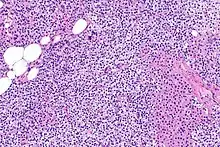

Primary hyperplasia of the parathyroid gland, results from both hypocalcaemia and increased phosphate levels by decreasing expression of calcium sensing receptors and vitamin D receptors at the parathyroid gland.[8][4] These decreases in receptor expression lead to hyperfunctioning of the parathyroid. Hyperfunction of the parathyroid gland is thought to exacerbate primary hyperplasia which evolves further to a secondary more aggressive hyperplasia. Histologically, these hyperplasic glands can be either diffuse or nodular.[24] Primary hyperplasia, usually resulting in diffuse polyclonal growth is manly related to reversible secondary hyperparathyroidism. Secondary hyperplasia of the parathyroid gland is more often a nodular, monoclonal growth that sustains secondary hyperparathyroidism and is the catalyst in the progression to tertiary hyperparathyroidism. Nodular hyperplastic glands in tertiary hyperparathyroidism are distinctly larger in both absolute size and weight up to 20-40-fold increases have been reported.[25][26][24]

Parathyroid glands are normally composed of chief cells, adipocytes and scattered oxyphil cells.[27][14] Chief cells are thought to be responsible for the production, storage and secretion of parathyroid hormone. These cells appear light and dark with a prominent Golgi body and endoplasmic reticulum. In electron micrographs, secretory vesicles can be seen in and around the Golgi and at the cell membrane. These cells also contain prominent cytoplasmic adipose.[27][14] Upon onset of hyperplasia these cells are described as having a nodular pattern with enlargement of protein synthesis machinery such as the endoplasmic reticulum and Golgi. Increased secretory vesicles are seen and decreased intercellular fat is characteristic.[27][24] Oxyphil cells also appear hyperplasic however, these cells are much less prominent.